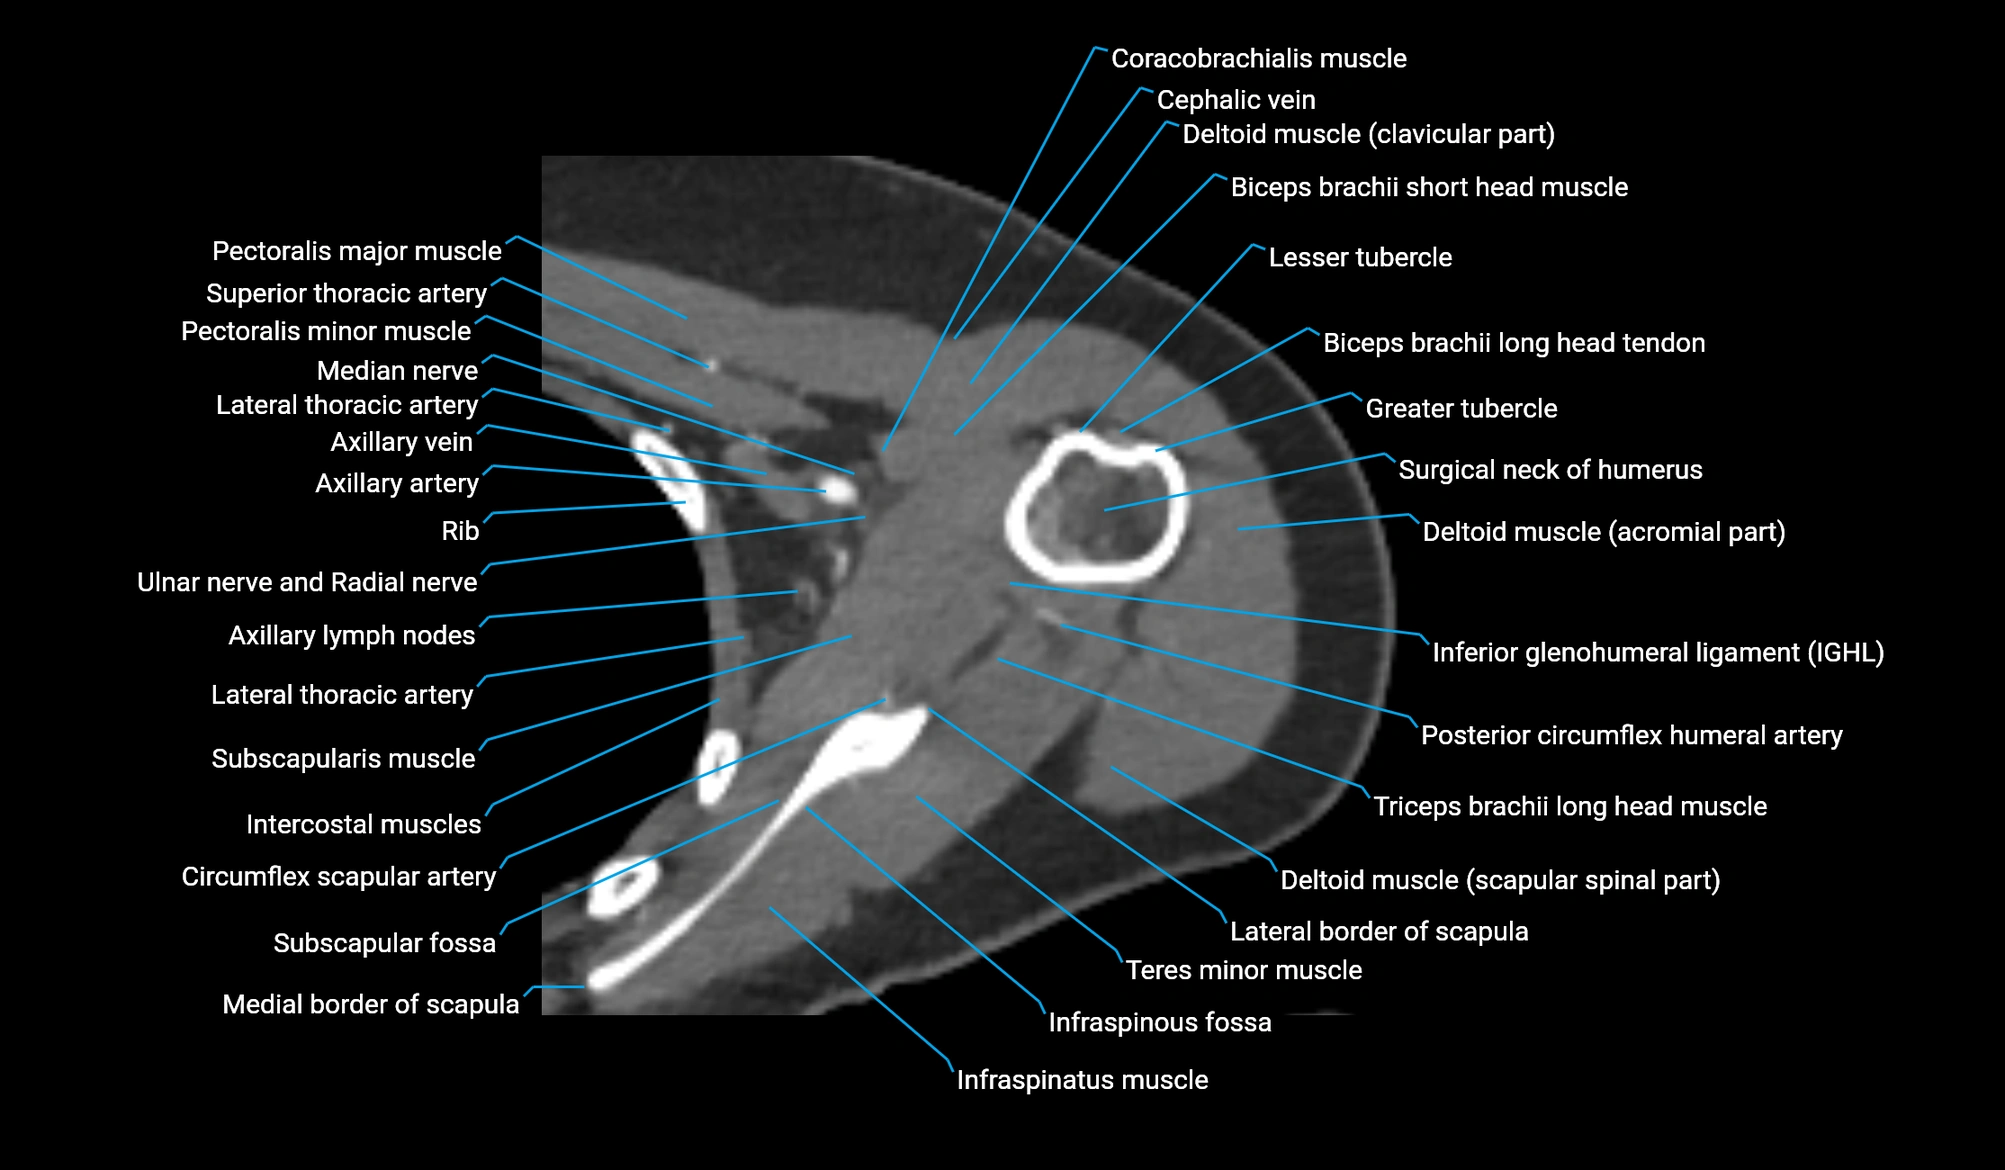

CT image